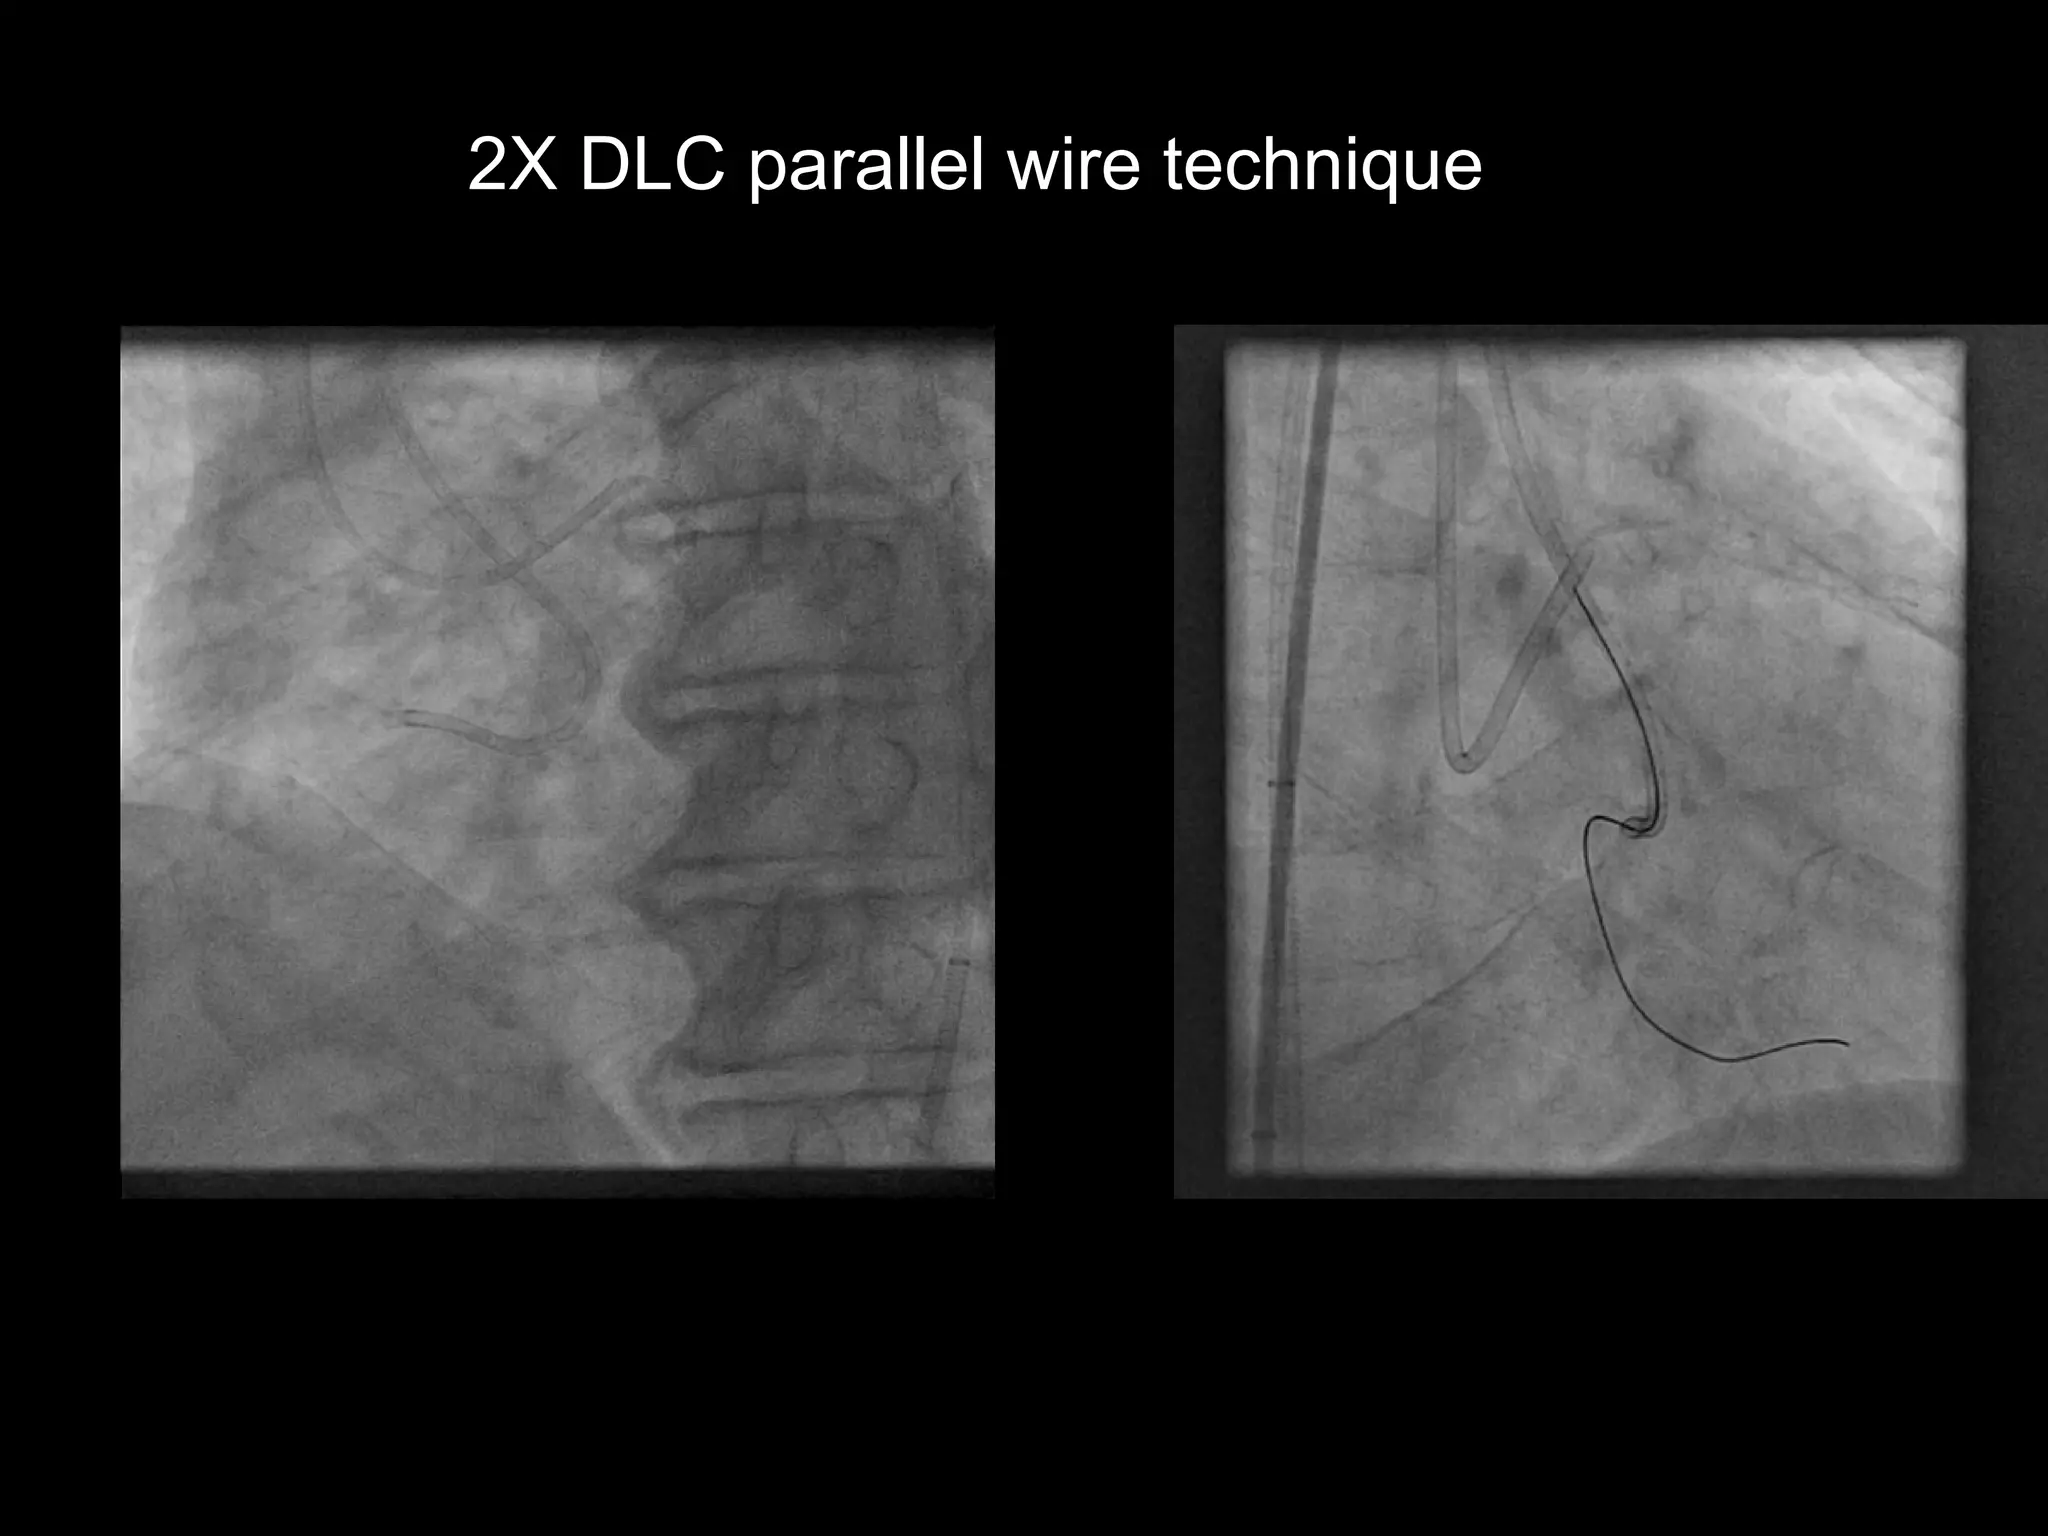

2X DLC parallel wire technique